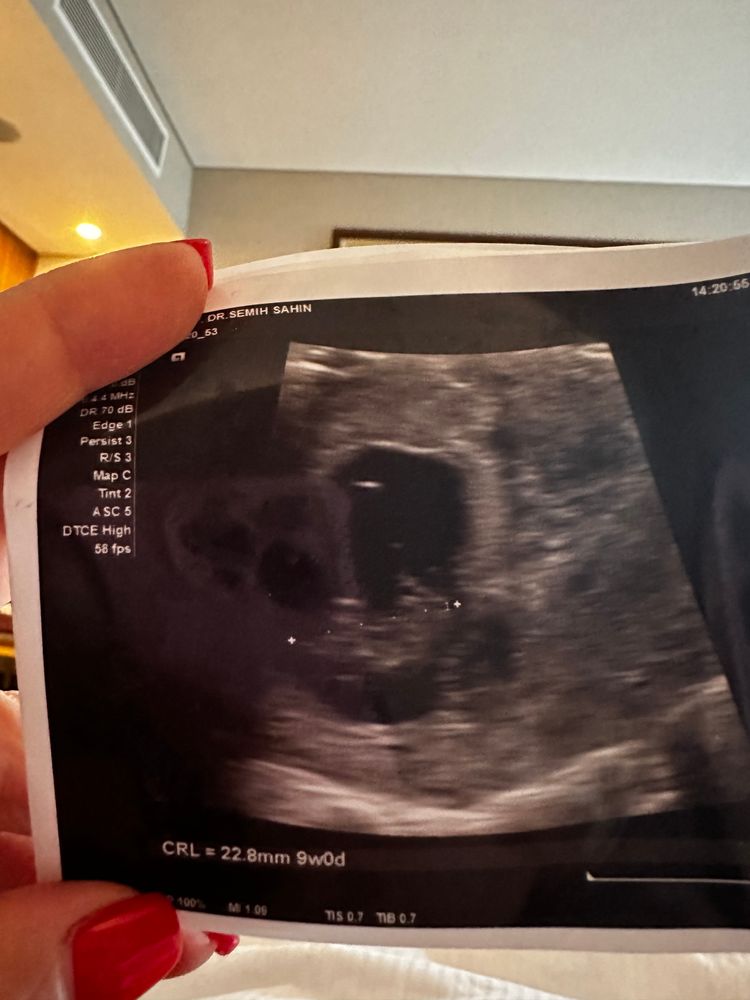

Алисия, один и тоже же и аппарат один, там на экране рост видно. Вот картинки Изображение Изображение